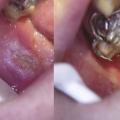

La primo-infection herpétique se traduit par une gingivostomatite aiguë survenant souvent pendant la petite enfance, mais elle n’est pas rare chez l’adolescent ou l’adulte jeune. Elle débute par de la fièvre, un malaise général, des douleurs pharyngées et gingivales ; des vésicules multiples parfois confluentes et polycycliques apparaissent sur une muqueuse érythémateuse. L’atteinte gingivale est constante (fig. 5 ) associée à des adénopathies cervicales sensibles. La guérison est spontanée en 2 à 3 semaines. L’herpès récurrent, dû à la réactivation du virus resté latent après la primo-infection, est souvent labial, classique « bouton de fièvre », précédé par une sensation de cuisson ou de prurit ; des vésicules groupées en bouquet se forment rapidement sur une zone érythémateuse, se rompent puis sèchent, formant une croûte jaunâtre. La fréquence est variable, favorisée par certains facteurs : stress, fièvre, cycles menstruels, traumatisme, exposition solaire… D’autres localisations bucco-faciales sont possibles telles que le seuil narinaire et les joues, la fréquence de la localisation intra-buccale est sous-estimée : gencives, palais (fig. 6 ). Le zona buccofacial est lié à la résurgence du virus varicelle-zona resté à l’état latent au niveau des ganglions sensitifs des nerfs crâniens (zona du nerf trijumeau) après la primo-infection varicelleuse. Il est plus fréquent chez les patients immunodéprimés. L’éruption, parfois précédée d’un syndrome infectieux modéré et de douleurs de topographie radiculaire, est vésiculeuse et intéresse le territoire d’un ou de deux troncs du nerf trijumeau. Le zona de la branche ophtalmique du trijumeau met en jeu le pronostic fonctionnel visuel.